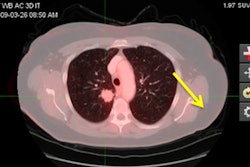

After excluding patients with enlarged lymph nodes as detected on MRI, the remaining cohort underwent a sentinel lymph node mapping procedure with preoperative Tc-99m nanocolloid SPECT/CT. By creating fused datasets of the SPECT and MRI, sentinel lymph nodes could be identified on MRI and accurately correlated with the histological result of each individual sentinel lymph node.

In 75 cases, 136 sentinel lymph nodes were analyzed; 13 nodes (10%) among eight patients contained metastases.